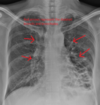

Rx en insuficiencia cardiaca

A: edema alveolar B: líneas B de Kerley C: cardiomegalia D: dilatación de vasos en lóbulos superiores E: derrame pleural

130

Insuficiencia cardiaca